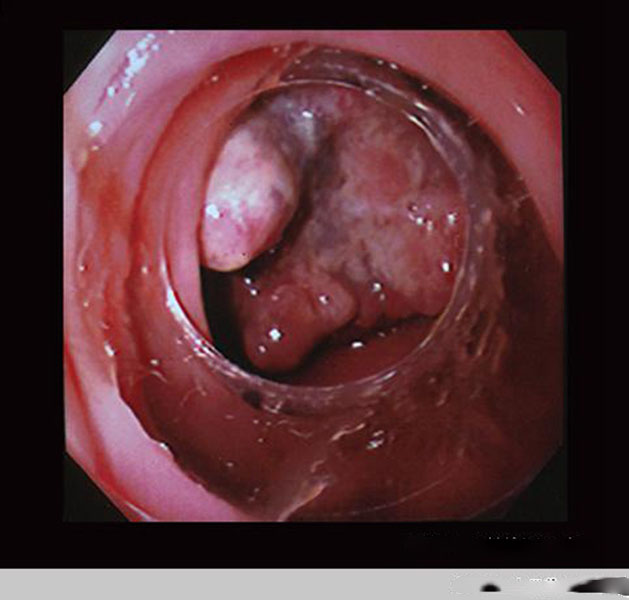

腸腫瘤圖片

直腸腫瘤惡性腸鏡

直腸腫瘤

直腸腫瘤早期

直腸腸腫瘤真實

直腸腸腫瘤後期